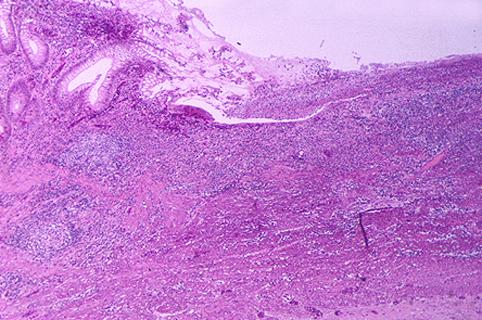

疾患(病理主体)の分類炎症性・潰瘍性疾患/クローン病

部位(臓器別)小腸/回腸

検査方法ミクロ